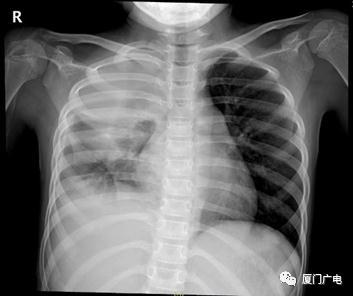

8岁的妍妍因高热、气急就诊

完善检查发现大量胸腔积液

入院立即行胸腔穿刺术

抽取胸水检出牙龈卟啉单胞菌

给予抗感染以及后续胸腔廓清手术治疗

患儿病情好转